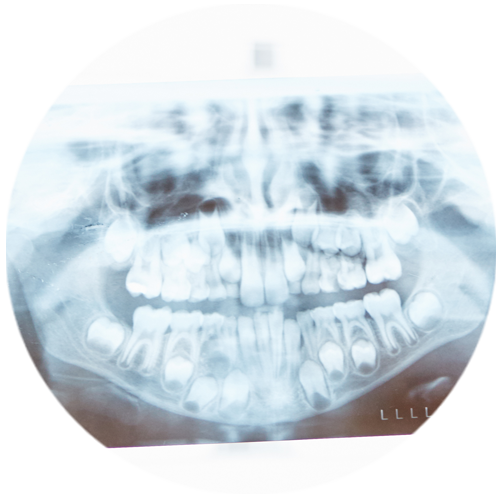

In many cases, removing wisdom teeth is very simple. When a tooth is impacted, it may still be removed simply, depending on the type and angle of the impaction. Because impacted teeth are near many important structures that we do not want to injure, such as the sinus or the nerve in the lower jaw, our office uses 3D imaging to see the exact location of these and other structures in relationship to the tooth. This minimizes risks and helps Dr. Duke find the best technique to remove the tooth as easily as possible. Many times, conventional imaging of the mouth may make it look safe, when the risks are actually higher.